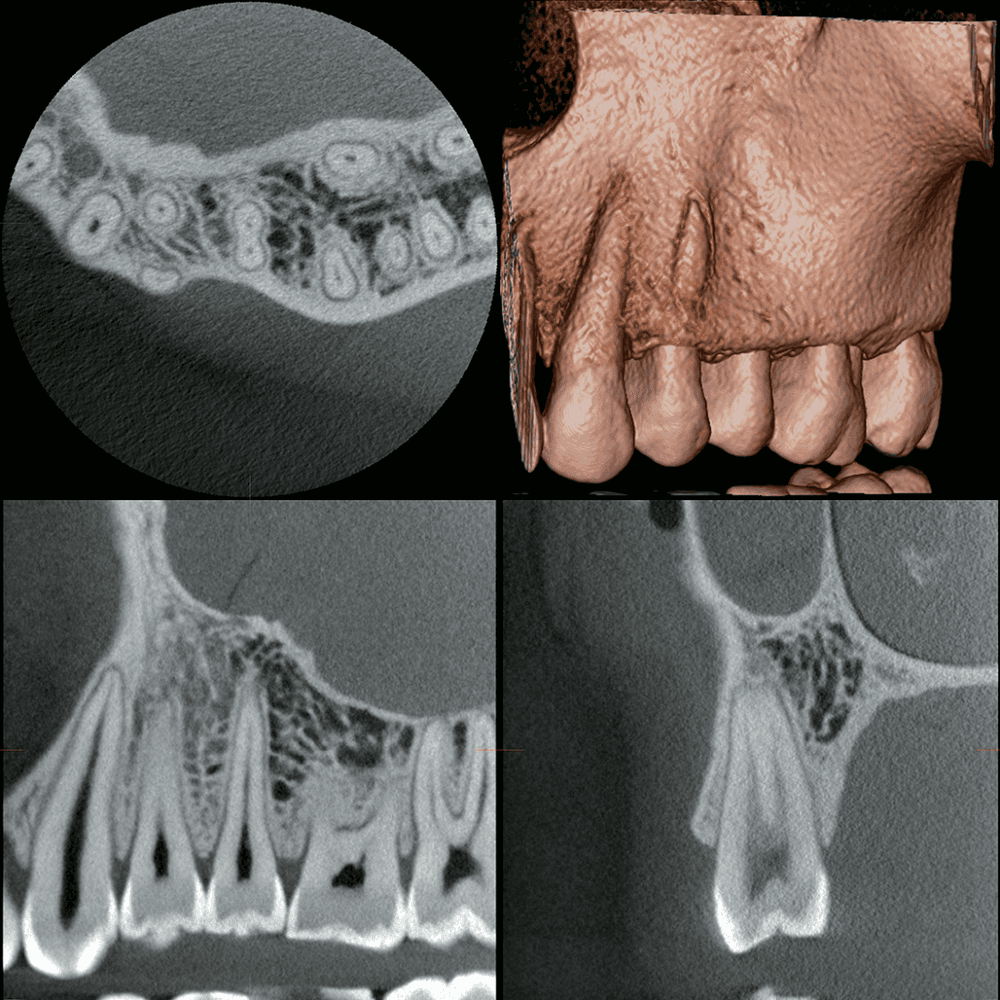

The J. MORITA Veraview X800 is an all-in-one 2D/3D imaging system that seamlessly integrates CBCT, cephalometric and panoramic imaging into one easy-to-use device. With 11 field of view options, cutting-edge technology and a design that prioritizes both patient and clinician ease, the Veraview X800 sets a new standard in dental imaging.

The J. MORITA Veraview X800 is a versatile all-in-one panoramic, CBCT and cephalometric workhorse, delivering superior image quality for precise diagnostics in both simple and complex cases. Designed to capture high-resolution dental X-rays, CBCT and cephalometric images, the Veraview X800 features 360° scanning (180° option for dose reduction) and an adjustable horizontal X-ray beam to minimize artifacts and enhance image clarity. Its expansive field of view ranges from ø40 to ø150, providing 11 options suitable for orthodontics, implantology, periodontology and endodontics. The Veraview X800 is also remarkably user-friendly, featuring direct, face-to-face patient positioning, a wheelchair-compatible design and an intuitive pictogram touch panel for easy operation.